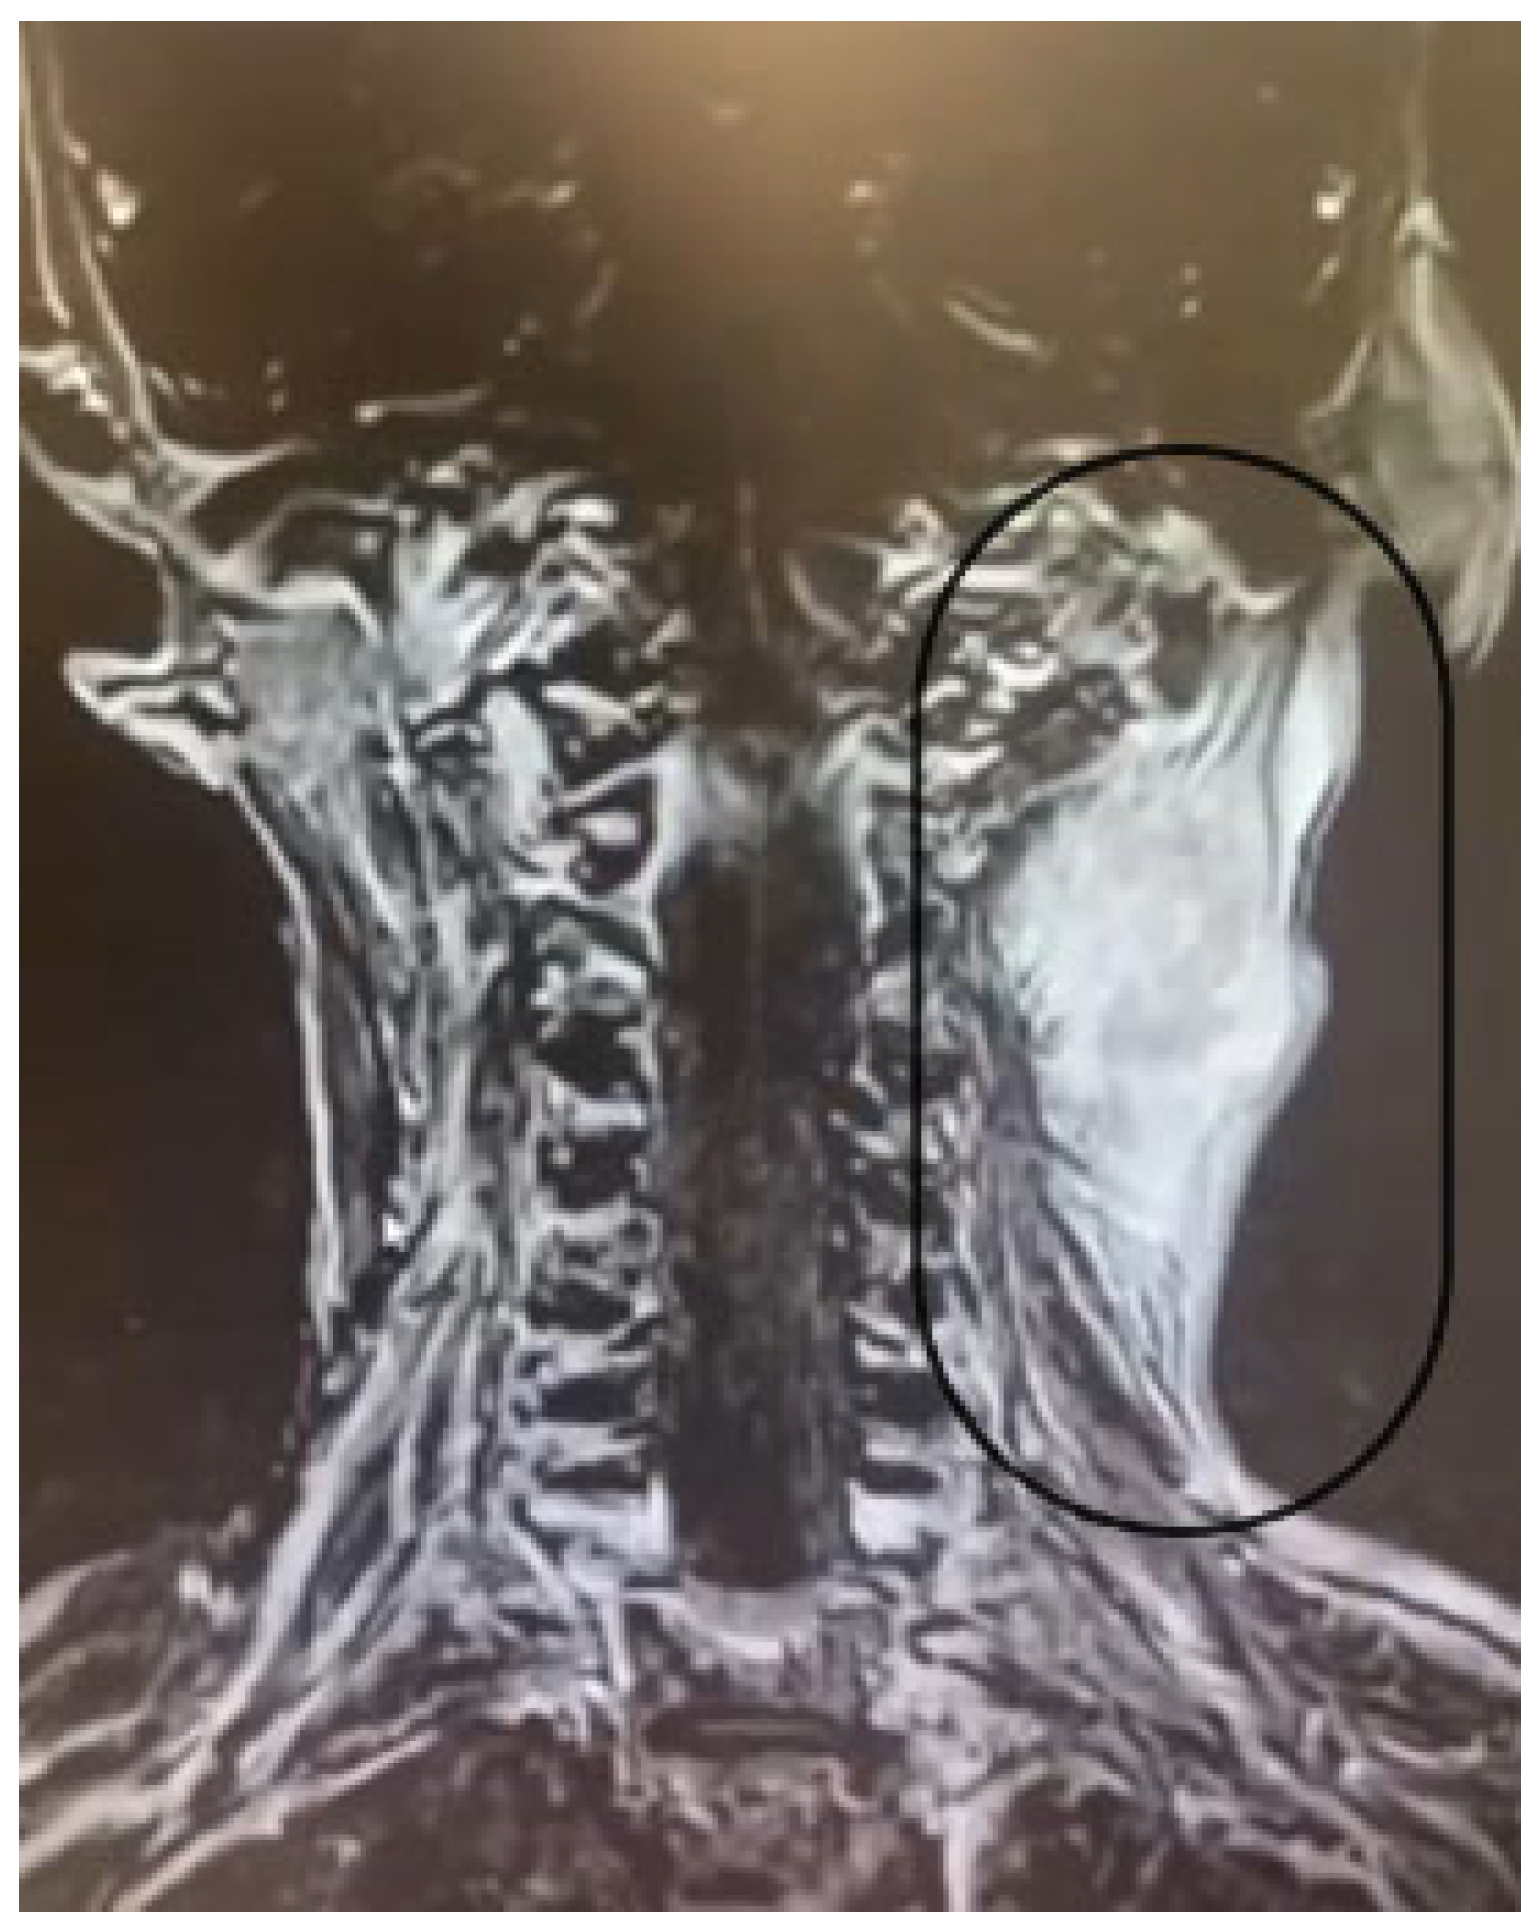

2.3.3. Imaging Findings